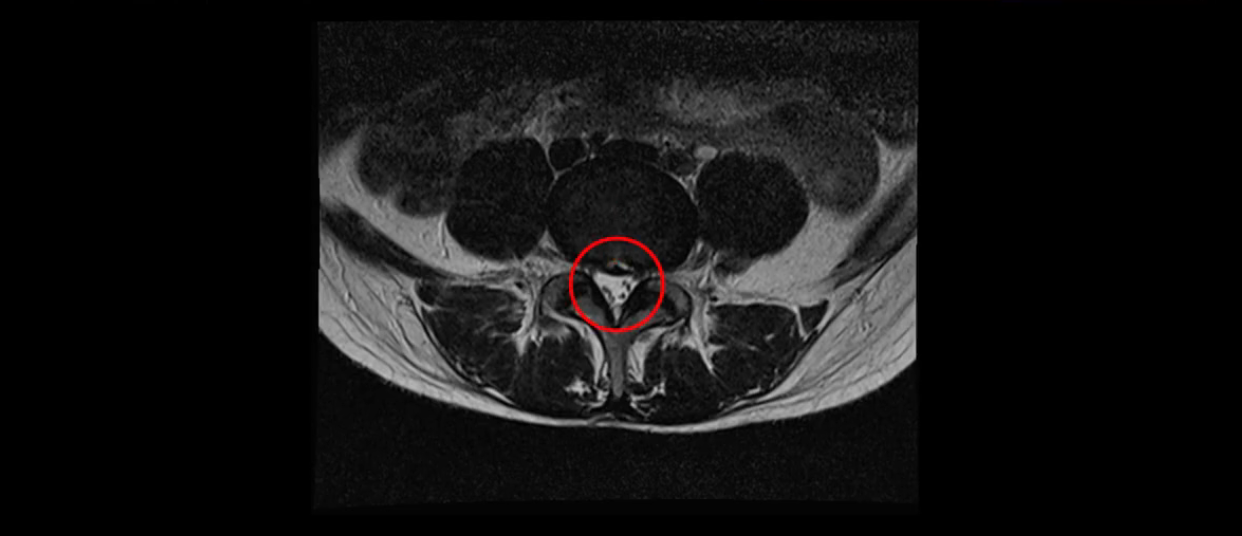

이분 MRI를 보시면 두 마디의 퇴행성디스크가 있습니다. 그리고 디스크가 조금씩 밀려 나와 있고요. 그런데 디스크 탈출 정도는 두 마디 다 심하지 않습니다. 4번 5번에는 디스크 탈출이 약간 있고,

척추관협착도 약간 진행이 되고 있고요.

5번 1번은 디스크 탈출이 가운데 쪽으로 살짝 있습니다.

또한 양쪽 신경 가지가 빠져나가는 추간공은 매우 넓은 상태입니다.

중요한 것은 이 정도 경미한 탈출과 협착으로는 양쪽 다리가 저리고 아플 수가 없습니다.

이분 MRI를 보시면 퇴행성디스크가 있고 약간의 협착이 있지만 이 정도의 퇴행성디스크와 협착으로는 신경이 눌려서 양쪽 다리가 저리고 아픈 증상이 나올 수가 없습니다. 그래서 MRI와 이 환자분의 다리 증상이 매치가 안 된다고 하는 의사들이 많은 겁니다.